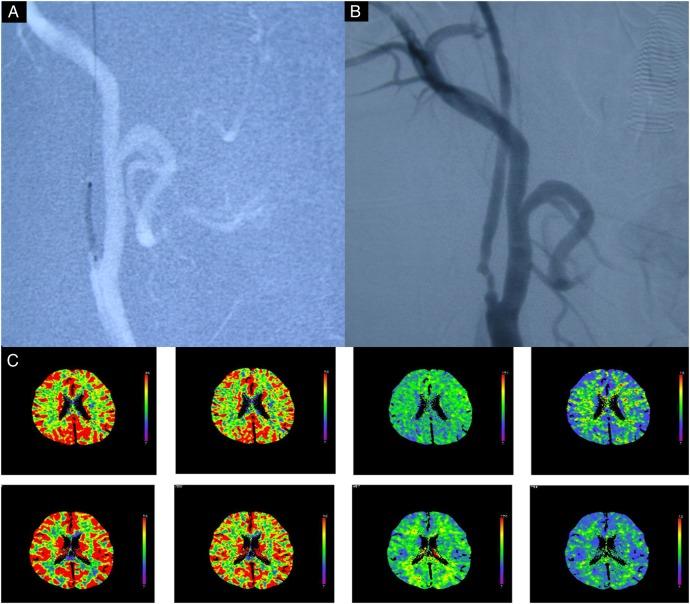

44 of 908 patients with high-grade internal carotid artery stenosis or near occlusion were at risk of HPS because of poor collateral flow and impaired cerebral blood flow (CBF). They were treated with first (stage 1), followed by a full CAS (stage 2) 1 month later. Their 30-day outcomes were tabulated and analysed.

During follow-up, 1 of the 44 (2.2%) patients developed HPS immediately, 3 (7%) had postprocedural HPS (ie, transcranial Doppler (TCD) >120%) without clinical symptoms and 3 (7%) required stenting at stage 1 for carotid dissections. After stage 1, there were significant improvement between the preprocedural and postprocedural CBF (0.98±0.06 vs 0.85±0.05, p<0.05), mean transit time (MTT; 1.05±0.05 vs 1.15±0.05, p<0.05), time to peak (TTP; 1.04±0.06 vs 1.20±0.06, p<0.05) on CT perfusion (CTP), and CBF (66.41±7.41 vs 44.44±6.43, p<0.05) on TCD. After stage 2, improvement was seen in CBF (1.01±0.07 vs 0.98±0.06, p<0.05), MTT (1.01±0.05 vs 1.05±0.05, p<0.05), TTP (0.99±0.06 vs 1.04±0.06, p<0.05) on CTP and CBF (66.41±7.41 vs 93.78±18.81, p<0.05) on TCD. 2 had postoperative increase of middle cerebral artery mean flow velocity of 120% after stage 2 without clinical symptoms.

在随访期间,44 例患者中有 1 例(2.2%)立即发生 HPS,3 例(7%)有术后 HPS(即经颅多普勒(TCD)>120%)而无临床症状,3 例(7%)在阶段 1 时因颈动脉夹层需要支架置入术。在阶段 1 后,CT 灌注(CTP)上的 CBF(0.98±0.06 比 0.85±0.05,p<0.05)、平均通过时间(MTT;1.05±0.05 比 1.15±0.05,p<0.05)、峰值时间(TTP;1.04±0.06 比 1.20±0.06,p<0.05)和 TCD 上的 CBF(66.41±7.41 比 44.44±6.43,p<0.05)有显著改善。在阶段 2 后,CBF(1.01±0.07 比 0.98±0.06,p<0.05)、MTT(1.01±0.05 比 1.05±0.05,p<0.05)、TTP(0.99±0.06 比 1.04±0.06,p<0.05)在 CTP 上和 CBF(66.41±7.41 比 93.78±18.81,p<0.05)在 TCD 上均有改善。有 2 例患者在阶段 2 后出现 MCA 平均流速增加 120%,但无临床症状。